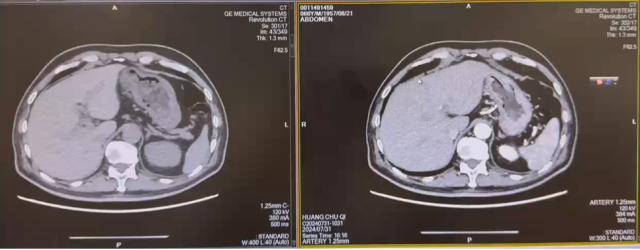

2022.1 靶免联合新辅助治疗

新辅助治疗前

新辅助治疗后

治疗后复查 CT(2022.7):左肾透明细胞 CA 治疗后改变,肿块较前缩小,强化程度减低,左侧副肾动脉可见;余况同前。